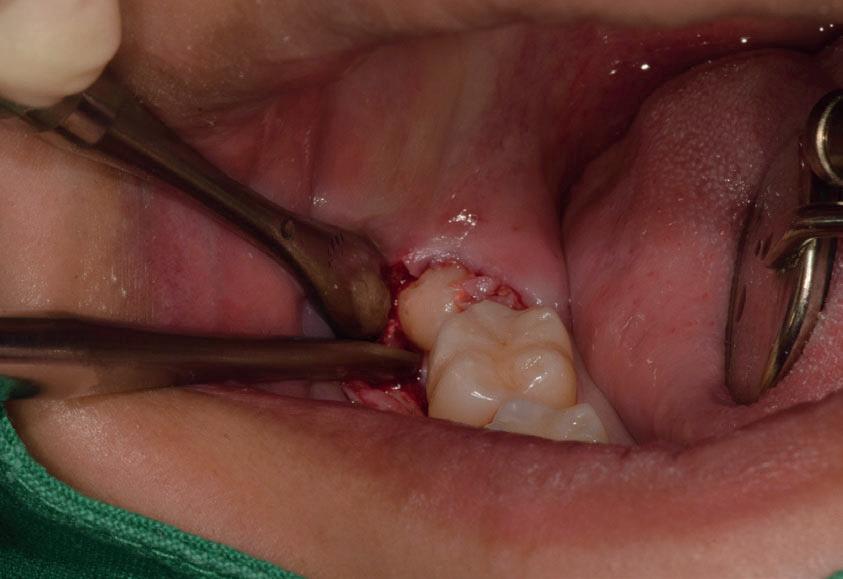

Il seguente caso chirurgico è di un 4.8 mesio-inclinato e parzialmente incluso. Dopo un’incisione a busta, il

dente è stato separato al centro per fare una coronectomia, prima della porzione distale e successivamente della porzione mesiale. Facendo leva quindi è stato possibile rimuovere le radici unite. Figg. 165-172

Figg. 165-172 - Caso 3: tecnica di estrazione con divisione orizzontale utilizzando il manipolo dritto. Fig. 165 Fig. 166 Fig. 167 Fig. 168 Fig. 169 Fig. 170 Fig. 171 Fig. 172